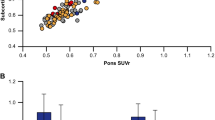

Composite cortical retention associations for the PiB–flutemetamol and PiB–florbetapir groups are shown for all three reference regions in Fig. 2. Spearman’s rho and slopes representing the linear regression for each tracer pair across cortical regions of interest (frontal, cingulate, parietal, temporal, and composite summary region) and with all three reference regions (brainstem, cerebellar grey matter, whole cerebellum) are also shown in the Supplementary table. The range of slopes for PiB–florbetapir associations was similar across all cortical regions of interest and reference regions (slope 0.59 – 0.66), indicating a narrower range of cortical retention values for florbetapir than for PiB. For PiB–flutemetamol correlations, on the other hand, slopes were closer to unity for the cerebellar grey matter-normalized (slope 0.79–0.83) and whole cerebellum-normalized values (slope 0.72 – 0.79), indicating similar cortical retention of PiB and flutemetamol when cerebellar reference regions were used.

Correlations between summary cortical composite retention ratios plotted for (a) subjects who received flutemetamol and PiB scans and (b) subjects who received florbetapir and PiB scans. Three reference regions (left brainstem/pons, centre cerebellar grey matter, right whole cerebellum) were used. Linear regression equations and Spearman’s rho are given for each correlation

Correlations between each pair of tracers were high (p < 0.001 in all cases) across all individual cortical regions examined, and no cortical region consistently showed the highest or lowest correlation. Correlations were highest with brainstem normalization (PiB–flutemetamol, ρ = 0.98 – 0.99 across cortical regions of interest; PiB–florbetapir, ρ = 0.95 – 0.97), compared to the correlations with cerebellar grey matter normalization (PiB–flutemetamol, ρ = 0.84 – 0.93; PiB–florbetapir, ρ = 0.83 – 0.86) and whole cerebellum normalization (PiB–flutemetamol, ρ = 0.88 – 0.95; PiB–florbetapir, ρ = 0.86 – 0.90). However, brainstem normalization also resulted in the lowest slopes overall (PiB–flutemetamol, slope 0.64 – 0.67; PiB–florbetapir, slope 0.61 – 0.66), indicating a reduced range of flutemetamol and florbetapir cortical retention relative to PiB.

The correlation and slope measurements derived from the PiB–flutemetamol and PiB–florbetapir associations provide complementary information. The correlation indicates how precisely the retention of one tracer in an individual can be estimated from another tracer’s retention. We found that correlations between each pair of radiotracers were highest with brainstem normalization and lower with cerebellar grey matter or whole cerebellum normalization (Fig. 2, Supplementary table). One possible explanation is that use of the brainstem reduces white matter retention variability between tracers and between individuals that is independent of the level of cortical retention (since brainstem white matter retention, unlike subcortical white matter retention, is not influenced by partial volume effects on cortical retention). The magnitude of the slope, on the other hand, indicates the degree of similarity between the range of cortical retention values for one tracer relative to another. Florbetapir cortical retention was lower than that of PiB across all reference regions (slope 0.61 to 0.65), whereas for PiB–flutemetamol, the slope varied: it was lowest for brainstem-normalized data (Fig. 1; 0.65) and higher for whole cerebellum-normalized and cerebellar grey matter-normalized data (0.72 and 0.81, respectively; Fig. 1). When normalizing cortical values by the brainstem (the reference region with the highest proportion of white matter) the higher white matter retention of flutemetamol compared to florbetapir reduces the cortical retention ratios more for flutemetamol, resulting in nearly identical slopes for PiB–flutemetamol and PiB–florbetapir.